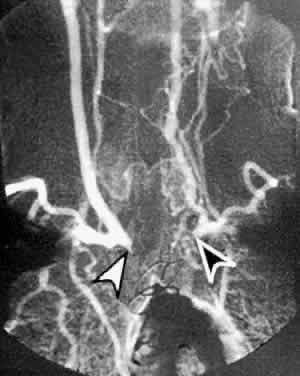

Prolonged arm-to-retina circulation times are frequently observed (Fig. 3B).24 This reflects the slower flow of blood from the carotid artery to the central retinal artery due to carotid occlusive disease. In normal persons, fluorescein dye is first detected in the retinal vasculature 12 to 15 seconds after dye is injected into the arm vein. Uncommonly, dye may take up to 20 seconds to reach the retinal arteries in a normal person. In ocular ischemic syndrome, arm-to-retina circulation times well over 20 seconds are not uncommon. The arm-to-choroid circulation time is also frequently prolonged in ocular ischemic syndrome because of the slow flow of blood from the carotid artery to the short posterior ciliary arteries. In pronounced cases, complete choroidal filling may still be lacking at 1 minute after injection. Accurate measurement of the arm-to-retina or arm-to-choroid circulation times requires experienced fluorescein angiography personnel, and these measurements depend on whether the dye was injected in the antecubital fossa or the hand, the rate of injection, and a reliable timer start time. Delayed or patchy choroidal filling may be seen in 60% of eyes affected with ocular ischemic syndrome (see Fig. 3B; Fig. 3C).1 Normally, the choroid is completely filled within 5 seconds after the initial appearance of dye in the choroid. Patchy choroidal filling greater than 5 seconds reflects sluggish blood flow through the short posterior ciliary arteries. In some cases, one or more quadrants of the choroid may display significantly slower filling than the other quadrants, indicating a relatively lower perfusion of individual short posterior ciliary arteries. Retinal arteriovenous transit time is measured from the initial appearance of dye within the retinal arteries in the temporal vascular arcade until the corresponding veins are completely filled. In normal patients, this occurs within 11 seconds; in ocular ischemic syndrome, the arteriovenous transit time is prolonged in approximately 95% of affected eyes (see Fig. 3B and C; Fig. 3D).1 Although this finding is relatively sensitive for a retinal vascular flow anomaly, it may also be seen in other vascular occlusive disorders, such as arterial and venous occlusive disease. Sometimes, a well-demarcated, leading edge of fluorescein dye within a retinal artery may be seen (Fig. 4B and C). This distinctly abnormal finding is seen in retinal arterial occlusion and ocular ischemic syndrome. In extreme cases of ocular ischemic syndrome, the retinal veins may fail to fill throughout the entire study. Staining of the retinal vessels can be seen in approximately 85% of ocular ischemic syndrome eyes in the later phases of fluorescein angiography (Figs. 4E, 5C, and 6C).1 The arterioles are usually involved to a greater extent than the venules. Hypoxic damage to the endothelial cells and pericytes may account for this phenomenon.11,25 In contrast to ocular ischemic syndrome, fluorescein angiography of eyes with central retinal artery obstruction rarely show late vascular staining. In CRVO, the retinal veins typically stain more than the retinal arteries.

ATHEROSCLEROSIS Atherosclerotic disease, because of its occlusive effects on the carotid arteries, is by far the most common cause of ocular ischemic syndrome. Histologically, there is thickening and hardening of the carotid artery caused by lipid-rich lesions within the innermost vessel layer.49,50 These lesions may partially or completely occlude the artery, either by slow growth or by a more rapid occlusion from hemorrhage into a plaque or thrombus formation. The most common site of atherosclerosis in the neck vessels is at the origin of the internal carotid artery. From this point, the atherosclerosis often propagates downward in a retrograde fashion into the common carotid artery. Less commonly, lesions may occur at the siphon, the S-shaped portion of the internal carotid artery that lies in the cavernous sinus. Rarely, the origin of the common carotid artery is the region affected. There is an association between atherosclerosis and increased levels of plasma lipoprotein, principally low-density lipoproteins.51 Risk factors for atherosclerosis also include cigarette smoking, systemic hypertension, diabetes mellitus, advancing age, male sex, obesity, stress, and type-A personality.52 In addition to its ischemic effects on the eye via carotid occlusion, atherosclerosis is responsible for the majority of cases of cerebrovascular accident and myocardial infarction, and it is therefore the leading cause of death in developed countries. Early diagnosis of ocular ischemic syndrome can therefore reveal underlying atherosclerotic disease in the carotid arteries or other parts of the body. Conversely, evidence of atherosclerotic disease in other parts of the body should raise the possibility of occlusive atherosclerotic carotid disease as well. CEREBROVASCULAR ACCIDENT Cerebrovascular accident, the third leading cause of death in developed countries, is most commonly caused by embolism or thrombus from an atherosclerotic carotid vessel. Thus, the ophthalmologist, in recognizing ocular ischemic syndrome, can play an important role in preventing a stroke by recognizing the effects of atherosclerotic carotid disease on the eye. Conversely, a history of stroke, especially of the middle cerebral circulation, may support a suspicion of ocular ischemic syndrome.53 Internal carotid emboli most commonly affect the middle cerebral artery or its branches, and they may result in paralysis and sensory impairment of the contralateral face, arm, and leg due to damage to the somatic sensory and motor cortices. Central aphasia, word deafness, anomia, jargon speech, sensory agraphia, acalculia, alexia, right-left confusion, and hemineglect may also occur. Homonymous hemianopsia may occur because of damage to the optic radiation deep to the temporal lobe. Paralysis of conjugate gaze to the opposite side may also be seen.54 AORTIC ARCH SYNDROME Aortic arch syndrome describes the clinical picture that results when multiple branches of the aortic arch are affected by a chronic occlusive narrowing of any etiology. Compromised blood flow through the brachial artery causes arm weakness, coldness, and claudications; involvement of the carotid arteries causes symptoms of cerebral or ocular ischemia. When the ophthalmologist encounters signs of ocular ischemia accompanied by symptoms of brachial insufficiency, aortic arch syndrome should be considered as the cause. The most common causes of aortic arch syndrome are Takayasu's arteritis, giant cell arteritis, and atherosclerotic disease affecting multiple branches of the aorta. TAKAYASU'S ARTERITIS Takayasu's arteritis is a rare, chronic inflammatory disease of unknown etiology affecting the large arteries of the body, namely the aortic arch, the descending aorta, the pulmonary artery, and their primary branches. It occurs mainly in young women, and the typical age of onset is 10 to 40 years.55 It appears in all populations, but is more frequently seen in Asians. The early signs and symptoms of Takayasu's arteritis include fatigue, weight loss, low-grade fever, arthralgias, myalgias, and headaches, and it may be mistaken for juvenile rheumatoid arthritis in a young female patient. The later clinical manifestations of Takayasu's arteritis relate to the anatomic site of vascular obstruction. Decreased blood flow to the brachial arteries results in coldness of the hands, paresthesias, and asymmetric or absent brachial pulses.56 Renovascular hypertension develops in half of patients because of involvement of the renal arteries of the abdominal aorta.57 Occlusion or narrowing of the carotid or vertebral arteries may result in cerebrovascular accident.58 Ophthalmic symptoms, due to ocular hypoperfusion from occlusion of the carotid artery, are seen in 15% of cases.59 These ophthalmic changes may be identical to those of ocular ischemic syndrome caused by carotid atherosclerotic disease (see Figs. 5 and 6).60,61 Arteriography of the aortic arch region, showing smooth-walled areas of stenosis and dilation, is usually necessary to confirm the diagnosis (Fig. 11). Collateral circulation, due to the chronicity of the stenosis, is usually prominent.